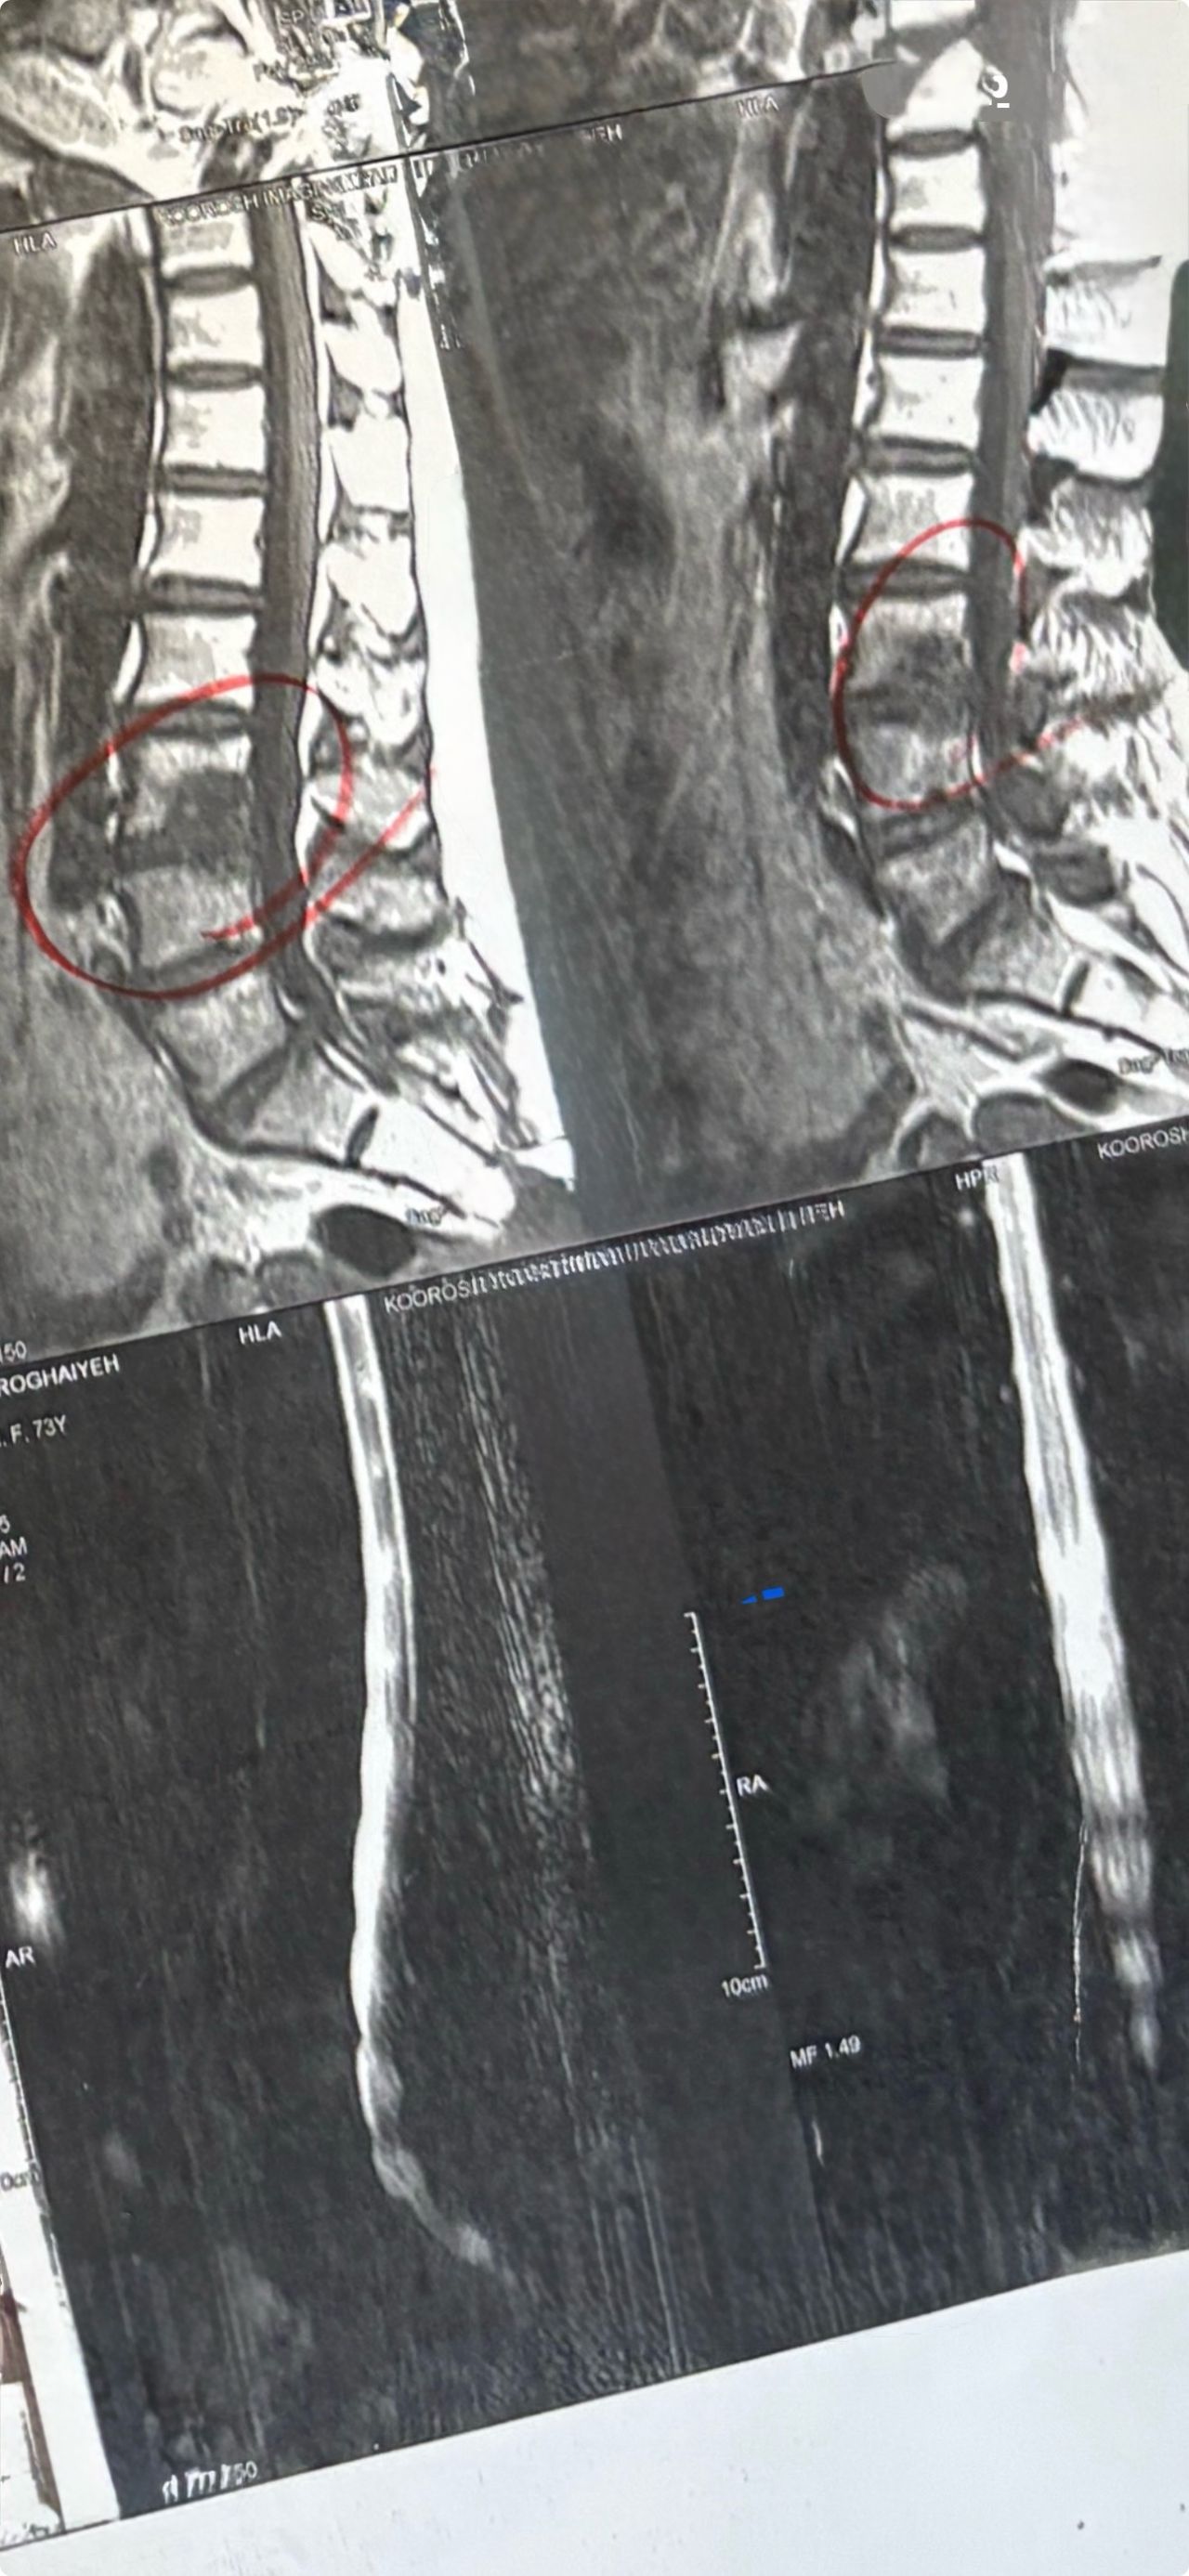

46 years old female patient presented to my clinic yesterday june 1/2025 with LBP and radicular L leg pain for several months which hasn’t responded to physio 2 neurosurgeons have visited her and didn’t suggest any surgery Neurological exam was unremarkable please see her mri/ emg/ncv and her huge tarlov cyst and possible L IVF L4-5 hyperbulge I ordered sacrum mri and ct scan and new emg/ncv and asked her with her sacral Ct scan and MRI first sees another two famous neurosurgeons and see if that large cyst is the reason for her pain if not i can work on her L4-S1 area Do you think her radicular pain can originate from her large cyst in sacrum? Do you consider surgery and removing her sacral cyst?